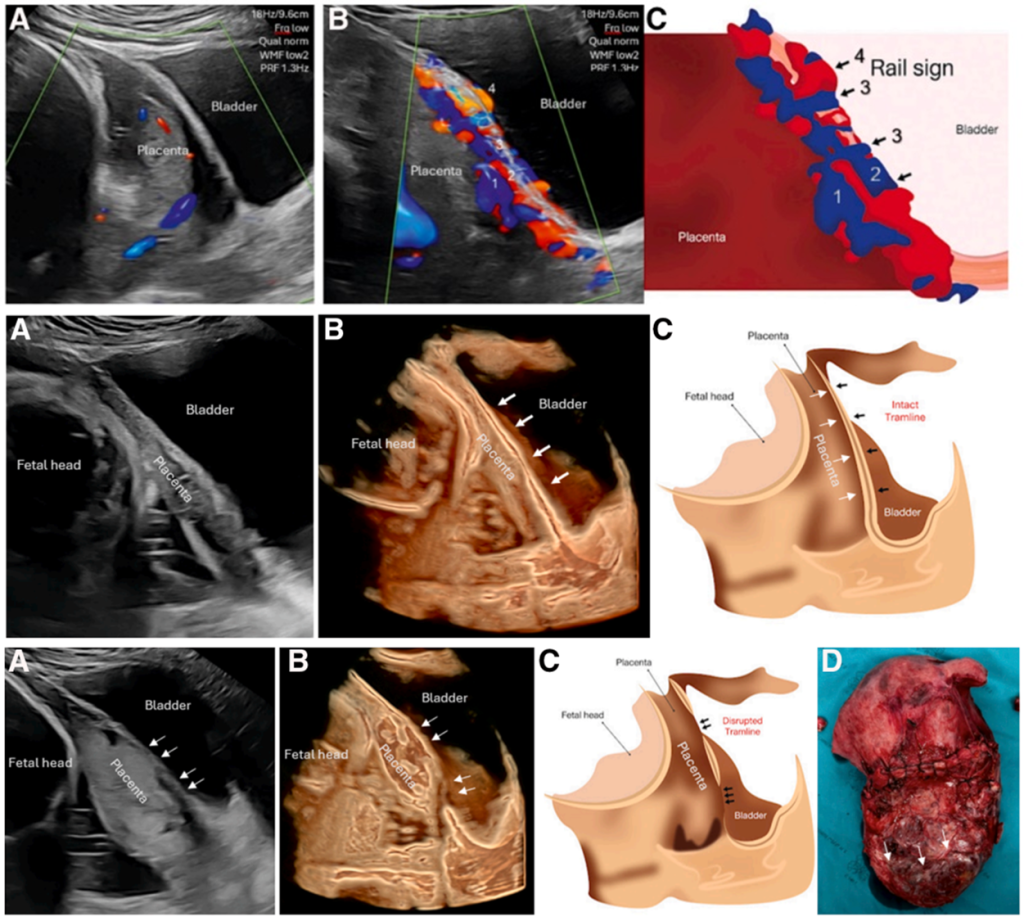

Dalam praktiknya, pemeriksaan ultrasonografi kini tidak hanya melihat bentuk plasenta, tetapi juga pola aliran darah untuk menilai tingkat keparahan spektrum plasenta akreta. Salah satu tanda yang digunakan adalah rail sign, yaitu gambaran dua garis sejajar pada pemeriksaan Doppler warna akibat peningkatan pembuluh darah di area antara plasenta, rahim, dan kandung kemih. Tanda ini menunjukkan adanya pertumbuhan pembuluh darah baru yang menghubungkan area tersebut, sehingga sering dikaitkan dengan invasi plasenta yang lebih dalam dan risiko perdarahan hebat saat persalinan.

Berbeda dengan itu, tramline sign dinilai melalui analisis pencitraan tiga dimensi tanpa menggunakan Doppler warna. Pemeriksaan ini melihat dua lapisan utama, yaitu batas dalam antara plasenta dan otot rahim serta batas luar antara rahim dan kandung kemih. Jika salah satu atau kedua batas ini tampak terputus, hal tersebut menandakan bahwa plasenta telah menembus lebih dalam, bahkan hingga mencapai lapisan luar rahim. Kondisi ini penting dikenali karena berkaitan dengan tindakan operasi yang lebih kompleks, termasuk kemungkinan pengangkatan rahim saat persalinan.